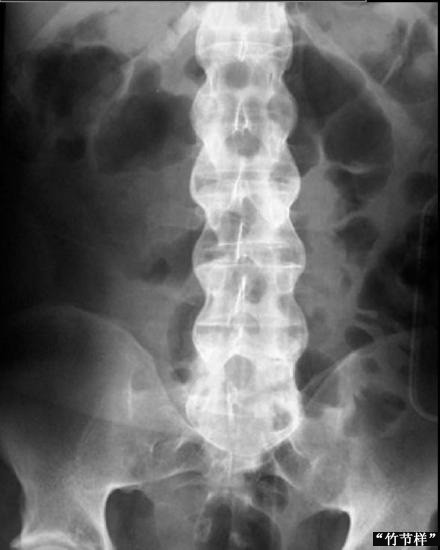

强直性脊柱炎是一种主要累及中轴骨骼的慢性进行性炎症性疾病,过去认为它是类风湿性关节炎的一种临床类型,故有“类风湿性脊柱炎”、“类风湿性关节炎中心型”等名称。现在多数学者认为它是一种独立性疾病,...[详细]